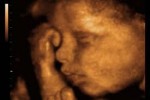

ULTRASSONOGRAFIAO ultrassom fetal confirma a vitalidade do bebê

O ultrassom fetal confirma a vitalidade do bebê, como detalha o especialista: “Além de detectar precisamente a idade gestacional, esse exame faz o estudo da morfologia fetal, o diagnóstico de gestação gemelar e o diagnóstico precoce de malformações fetais graves e de gestações múltiplas”.